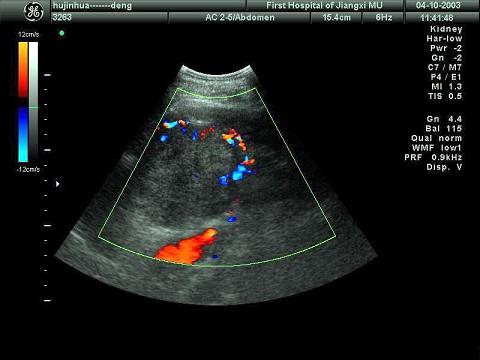

某患者肝脏发现肿块回声,根据CDFI声像图表现,最可能的诊断是?(?)A.肝血管瘤B.肝脓肿C.肝炎性假瘤D.肝囊肿E.肝癌

选项 A.肝血管瘤 B.肝脓肿 C.肝炎性假瘤 D.肝囊肿 E.肝癌

答案 E